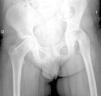

La gravedad de la ECF se mide de 2 maneras. El desplazamiento de la epífisis respecto a la metáfisis es el porcentaje de desplazamiento de la cabeza femoral respecto al cuello. Este desplazamiento puede ser leve (<33%), moderado (33–50%) y grave (>50%) (fig. 3). Aunque se utiliza de forma frecuente, presenta una gran variabilidad inter-intraobservador, además de estar influenciado por la posición del paciente. Southwick describió el ángulo epífisis-diáfisis en la radiografía anteroposterior y axial de ambas caderas. Se traza una línea a través de la superficie fisaria de la epífisis y se dibuja un ángulo recto a partir de esa línea. A continuación, se traza una línea paralela a la diáfisis del fémur. El ángulo formado por estas dos últimas líneas es la medida del desplazamiento posterior. Se resta el ángulo obtenido en la cadera sana del ángulo en la ECF, obteniendo así el grado de desplazamiento. El grado de deslizamiento se clasifica como leve (<30%), moderado (30–50%) y grave (>50%) (fig. 4).